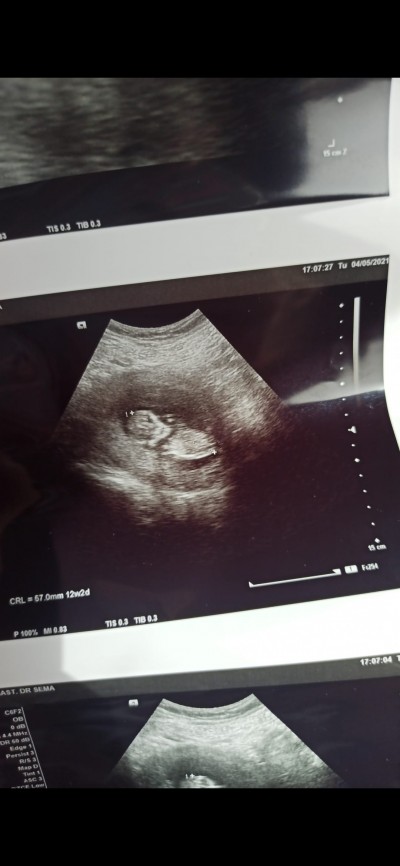

Bakarmisin lütfen

Cinsiyet tahmini edermisiniz

Gebelik haftası

12

canim inanki hicbisey anlamadim ama icimden erkek gecti hakkinizda hayirlisi

Ultrosonda ilk haftalar böyle net çıkarsa erkek derler bana öyle demişlerdi . Net çıkmış senin kide. Hakkında hayırlısı olsun .

Benimkide netti ama kizim olucak onla alakasi yok bence

Burda bebegin arkası dönük görünen birşey yok kafasi belli oluyor secdeye eğilmiş gibi gözükmüyor ki